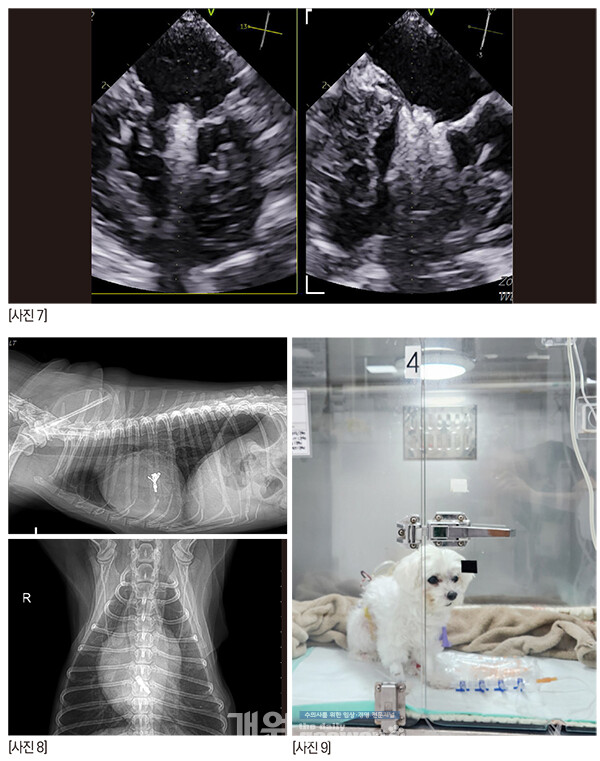

짱아의 수술은 난도가 높다는 판단이었다.

알박사가 ‘risk’라고 하면서 술자들에게 한번 더 주지시킨 이미지이다. 화살표들은 조심해야 하는 부분들 혹은 판막의 심한 퇴행성 변화를 의미하는 곳이다. 이렇게 되면 우리에게는 정답 zone은 딱 하나다.

판막을 가로지르는 저 화살표. 저 곳밖에는 답이 없다. 힘든 수술이 될 것이었다.

술자가 수술을 타이트하게 준비하고 각오를 하면 아이러니하게도 수술이 별일 없이 흘러간다. 마치 수혈 준비를 하고 수술을 하면 수혈할 일이 안 생긴달까[사진 7].

다행히 정답 zone에 안착했다.

[사진 8] P1-2 사이의 deep cleft like indentation 때문에 역류는 조금 남겠지만 술 전보다 나은 상황으로 만들고, 거기서 더 이상 진행만 안되면 충분히 괜찮다.매우 매우 걱정했지만 다행히 수술은 무사히 끝났고, 브이클램프를 close하는 시도도 한번으로 끝났다.